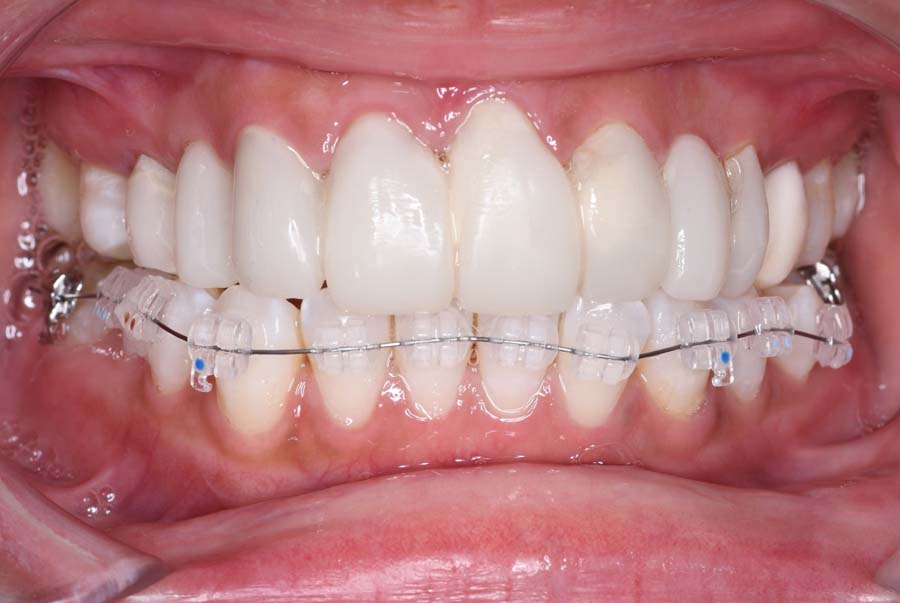

| 治療内容 | ①スプリントを装着 ②副子を装着 ③2024年4月 口腔内反映開始 ④副子を入れた状態の所まで咬合を挙上 (バイトアップ) ⑤2024年5月 上顎前歯部8本へ仮歯(TEK) を装着 |

2024年 10月 下顎MTM開始